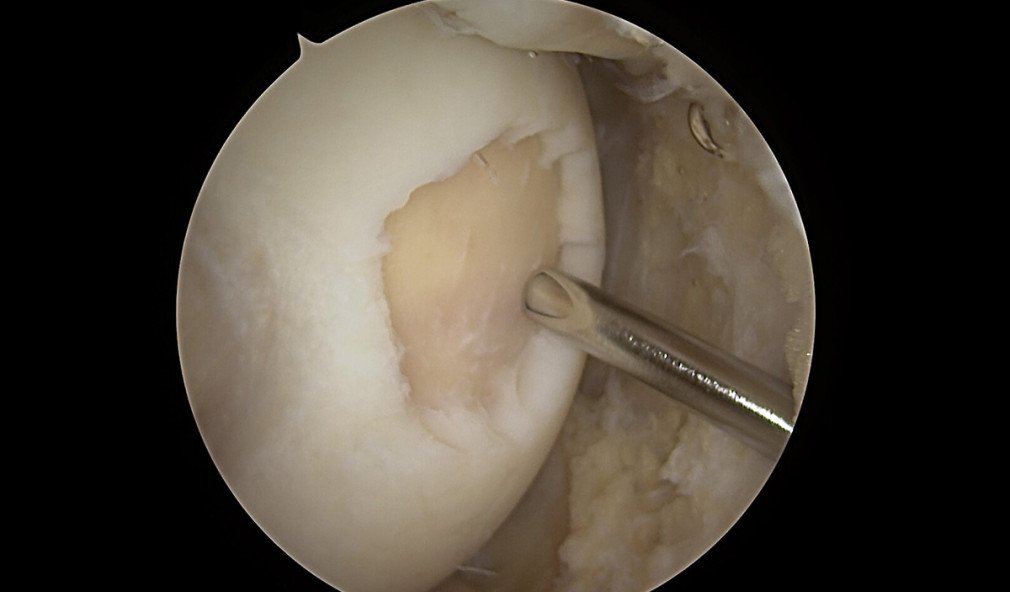

Knorpelschaden Knie: Aufbereitung für Knorpelchips-Implantation

Knorpelchips-Implantation (Minced Cartilage): die elegante, schonende Knorpelreparaturtechnik

Ein neu entwickeltes Knorpelreparaturverfahren zeigt vielsprechendende Ergebnisse, um Knorpelschäden am Knie zu reparieren. Bei der Knorpelchips-Implantation wird eigenes Knorpelgewebe mechanisch in «Chips» zerkleinert, mit dem zuvor aufbereiteten eigenen Blut des Patienten vermischt und wieder eingesetzt.